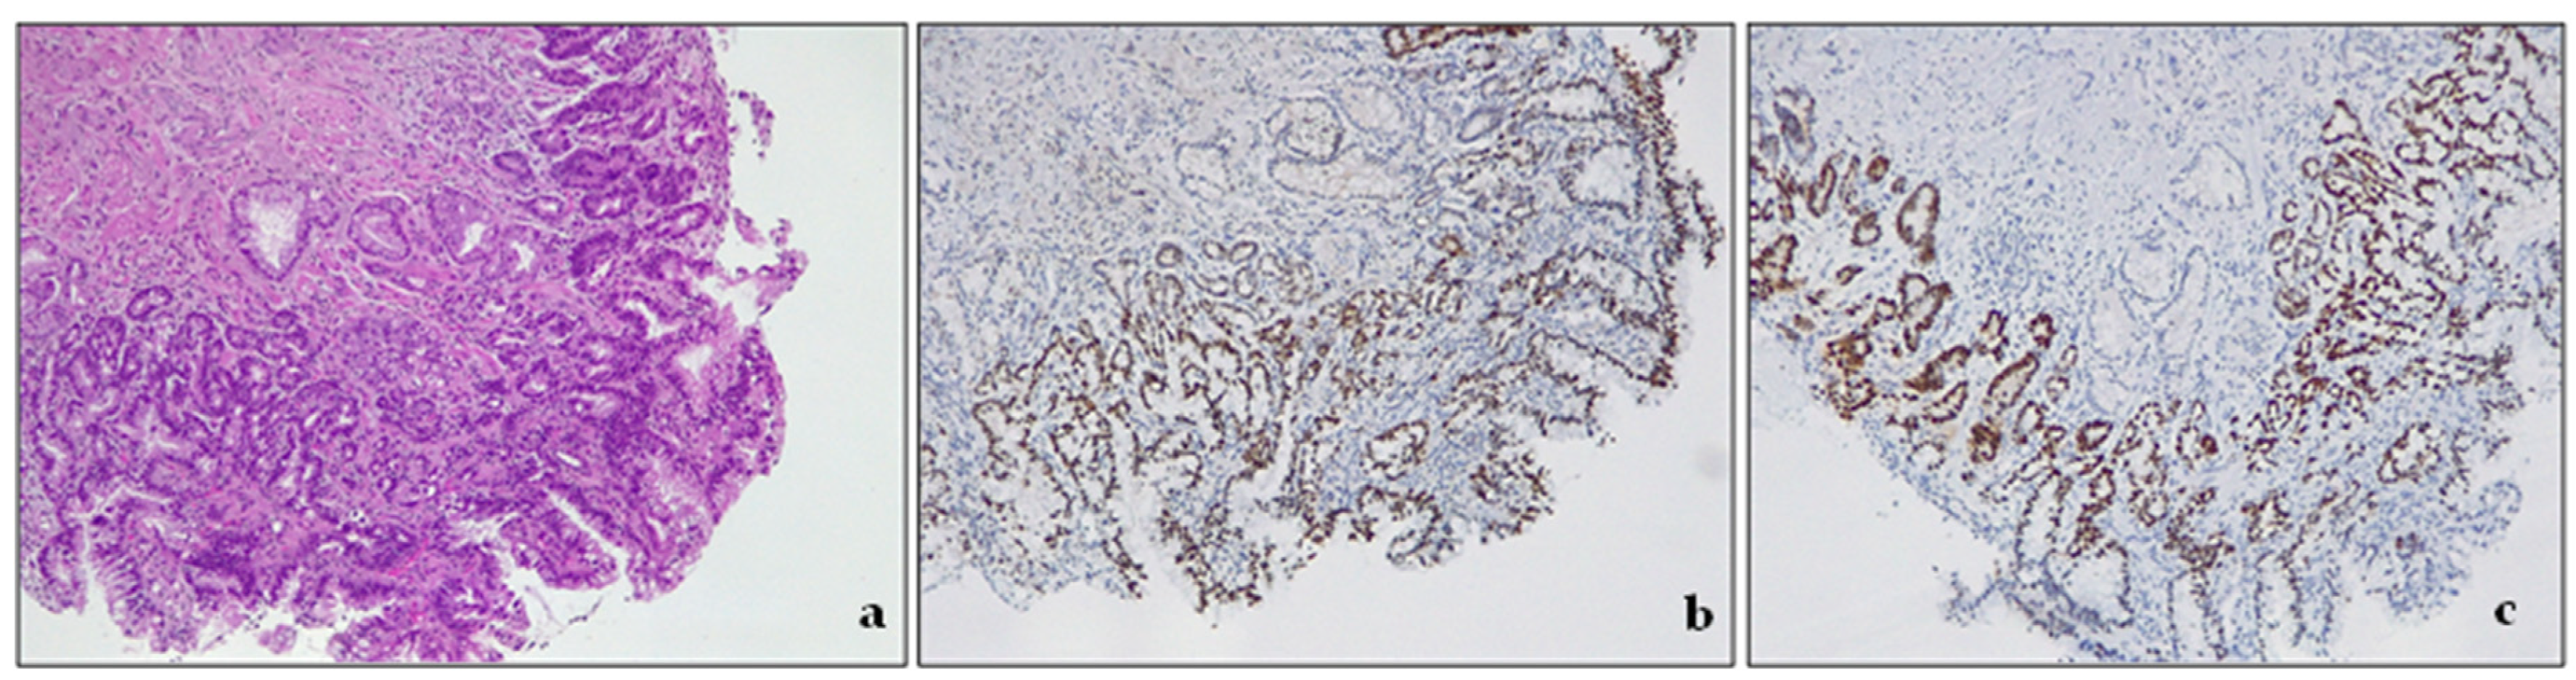

Low-grade dysplasia (LGD) is a pathological condition characterized by cells with nuclear enlargement, elongation, hyperchromasia, and stratification but with retained nuclear polarity (Figure 4). The dysplastic crypts typically show minimal architectural changes, and there is still evident lamina propria between them. The nuclei are slightly enlarged, and the number of mitoses generally increases, but they still appear normal. The cytoplasm is usually eosinophilic and depleted of mucin. The number of goblet cells may vary from very few to numerous [3,43].

Figure 4.

Intestinal type dysplasia, low grade. (a) The glands are packed, but lamina propria is still detectable between the glands. There are some scattered residual goblet cells. H&E. Original magnification 200×; (b) CDX2 expression in metaplastic glandular epithelium, devoid of goblet cells. Original magnification 200×; (c) p53 expression in metaplastic glandular epithelium, devoid of goblet cells. Original magnification 200×.

- Low-grade dysplasia—LGD. The cells in LGD display nuclear enlargement, elongation, hyperchromasia, and stratification, but their nuclear polarity is retained (Figure 4). Although the dysplastic crypts show minimal architectural changes, the lamina propria between them is still visible. The nuclei are slightly enlarged, and the number of goblet cells present may range from a few scattered ones to numerous.